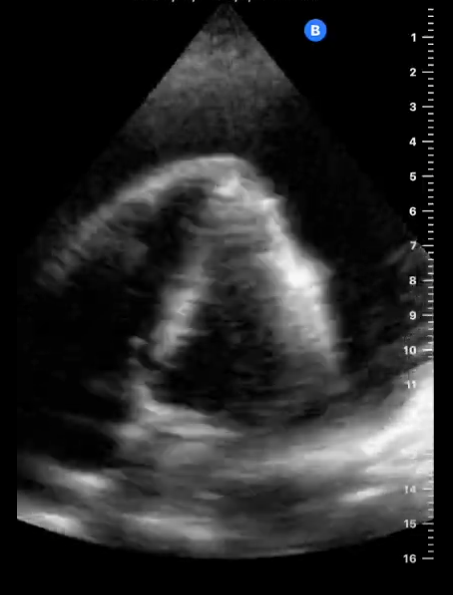

En la ecocardiografía se aprecia latido cardiaco con intercambio de flujos muy disminuido y el miocardio movilizándose en el interior del derrame pericárdico contenido sin taponamiento.

En este caso tenemos un cuadro de derrame pericárdico con repercusión hemodinámica pero apreciándose latido cardíaco y suficiente contractilidad como para no incurrir en taponamiento cardíaco que hubiera supuesto una emergencia vital para la paciente.